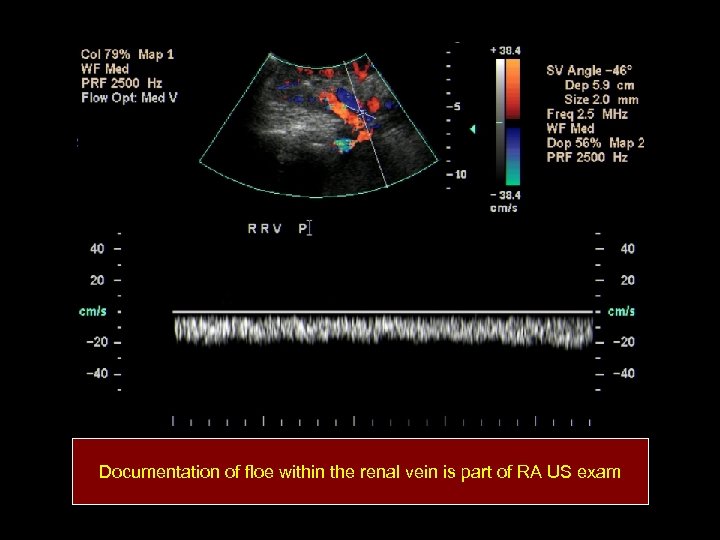

Documentation of floe within the renal vein is part of RA US exam